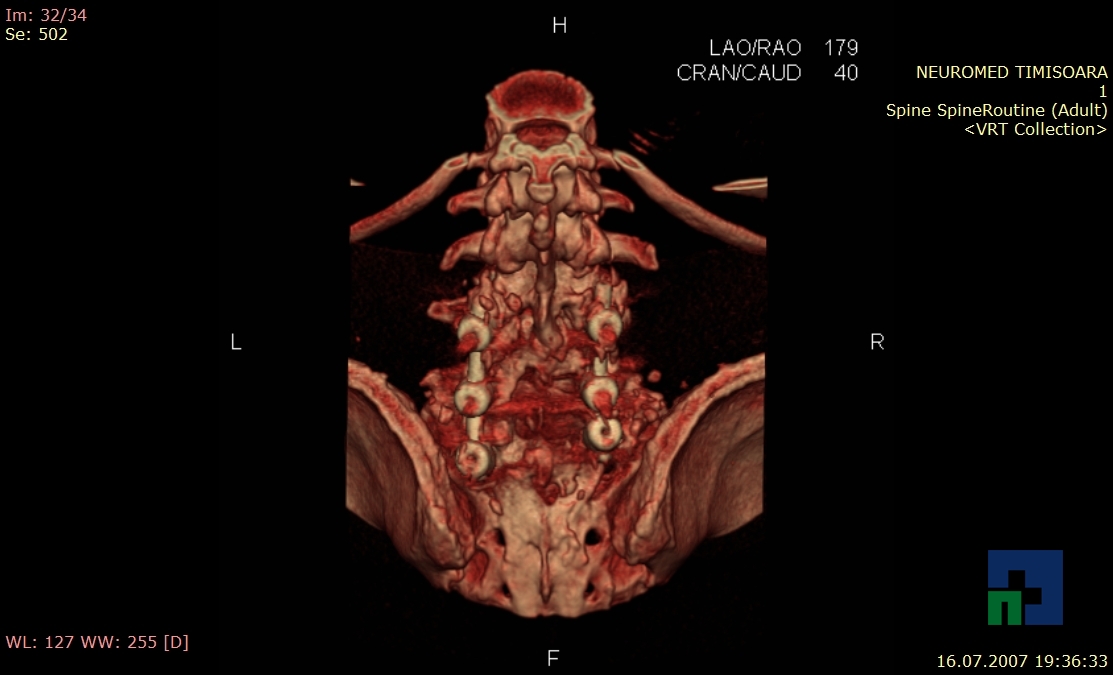

- Diagnosticul fracturilor:

-

- Unice

- Multiple

- Cu înfundare

- Complexe cranio-sinusale

- Complexe cranio-etmoidale

- Complexe cranio-orbitare

- Complexe cranio-faciale